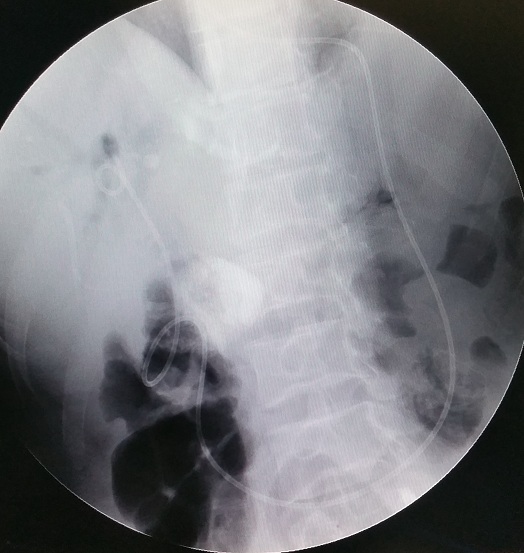

昨日,我们采用ERCP手术,成功为一位实施过胰十二指肠切除术的胆管结石患者实施了ERCP取石治疗。

患者男性,45岁,主因“突发上腹痛1天”于2016-7-31就诊于我院。患者8年前因“胰头占位”于外院行开腹胰十二指肠切除术,6年前和4年前分别因胆总管结石行开腹胆总管切开取石术。急诊上腹部CT示:肝内外胆管扩张,胆总管结石,大小约1.0cm*0.9cm。综合以上结果诊断明确为:1.胆总管结石伴急性胆管炎 2.胰十二指肠切除术后 3.胆总管切开取石术后。

昨日,为患者进行ERCP手术并成功取净患者肝内外胆管结石。手术过程中,患者生命体征平稳,手术取石顺利。胰十二指肠手术中复杂的吻合会给医生在进镜过程中带来许多困惑,由于胆管、胰管和十二指肠被中断,至少需要建立3个独立的连接,以重建胰腺、胆管和消化道的连续性,自胃肠吻合口的输入袢进镜先连接胆管而后连接胰管。本例患者不但发现胆肠吻合口,还意外发现了胰肠吻合口。手术改变了解剖结构寻找胆肠吻合口是一个困难的过程,发现了胆肠吻合口后应用取石网篮、取石球囊取净了肝内外胆管结石。要成功的完成操作,熟悉患者既往手术方式、充分的术前计划、足够的配件配备和精湛的技术同样重要。此例手术的成功实施是在复杂病例ERCP微创治疗方面的又一次突破。